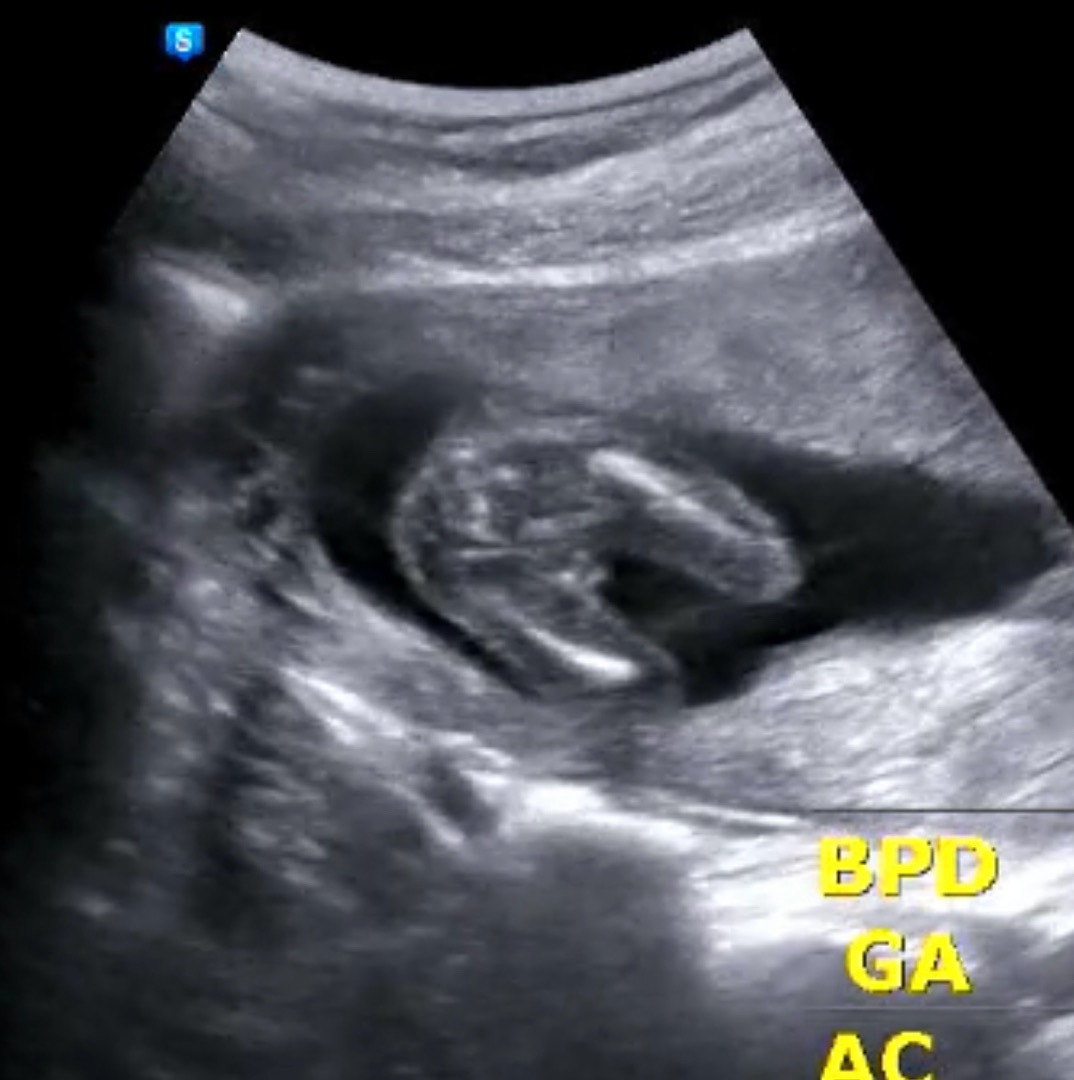

16주3일차 병원가서 성별 확정 받고 왔어요 선생님께서 언급 안해주셨는대도 너무 존재감 뿜뿜이라ㅎㅎ 요즘 주변에서 다들 딸을 많이 원하시던대 귀한 아들이라 생각합니다 하핳💕